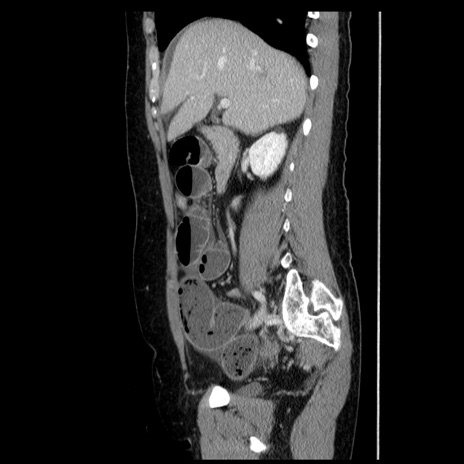

症例6(矢状断像)

【症例】50歳代女性

【主訴】下腹部痛

【現病歴】本日朝より下痢2回あり。 昼食を食べた後、嘔吐3回、下腹部痛認め、症状軽快せず、当院救急搬送。

最終食事:本日昼(生ものなし)。 昨日の夜、刺身を食ぺたとのこと。周囲に同様の症状の者なし。普段、排便は毎日あるとのこと。

【既往歴】卵巣癌術後(8年前に当院で卵巣摘出)

【身体所見】 意識清明、腹部:平坦、腸蠕動音→、やや硬、下腹部自発痛・圧痛あり、反跳痛あり、筋性防御なし。

【データ】WBC 16000、CRP 0.01